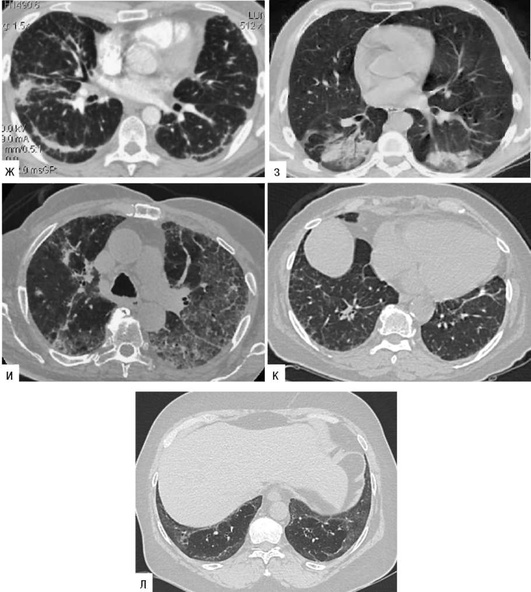

Лучевые методы исследования. Рентгенологическая картина при ЭТА зависит от стадии заболевания. В начальной фазе выявляются признаки отека интерстициальной ткани легких и распространенные мелкоочаговые затенения. При прогрессировании процесса формируются двусторонние изменения легочного рисунка по типу интерстициального фиброза, преимущественно в нижних отделах легких (рис. 2.28). В далеко зашедших случаях определяется мелко- и крупноячеистая деформация легочного рисунка. Описаны случаи, когда единственным рентгенологическим признаком болезни был односторонний плевральный выпот. Отсутствие каких-либо изменений на рентгенограммах отнюдь не исключает ЭТА. Так, при бериллиозе у 23-59% больных может выявляться умеренно выраженная двусторонняя лимфоаденопатия, а в ряде случаев - рентгенотрицательная форма бериллиоза (Dweik R.A., 2015). У 30% из 71 больных ЭТА, наблюдавшихся нами в клинике пульмонологии, в момент обследования изменений на рентгенограммах не было (Орлова Г.П., 2019). Группа больных ЭТА была обозначена условно как рентгенотрицательная группа. Уточнить диагноз помогает КТ легких, выявляющая интерстициальные изменения в легочной ткани по типу «матового стекла», усиление и деформацию легочного и сосудистого рисунка (рис. 2.29), фиброзные изменения тяжистого и звездчатого типов, на поздних стадиях - «сотовое легкое». ВРКТ выявляет «матовое стекло» и другие изменения в легочной паренхиме, которые не видны при обычном рентгенологическом исследовании. Но даже ВРКТ не всегда выявляет изменения в легочной ткани. Так, в 25% случаев гистологически подтвержденного хронического берил-лиоза легких ВРКТ была нормальной (Dweik R.A., 2013; Амосов В.И., Сперанская А.А., 2015; Amanullah S. et al., 2015).

Проведенное нами динамическое исследование КТ-паттернов у 42 больных ЭТА показало трансформацию отдельных типов интерстициальных пневмоний по мере прогрессирования патологического процесса в фиброзную НСИП или ОИП (рис. 2.30), что подтверждает объединительную концепцию интерстициальных пневмоний вне зависимости от этиологического фактора, которые являются не отдельными нозологическими формами, а стадиями течения фиброзирующего процесса в легких (Илькович М.М., Новикова Л.Н., 2018; Орлова Г.П. и др., 2019).